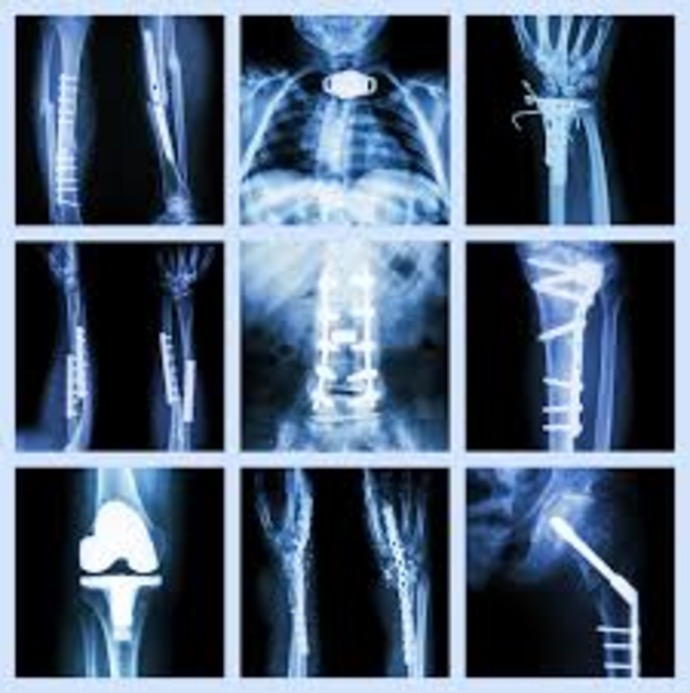

Fracture Management

- Simple fractures – closed reduction, casting, or bracing

- Complex fractures – open reduction and internal fixation (plates, screws, rods, nails)

- Multiple fractures (polytrauma) – staged surgeries and stabilization

- Pelvic & acetabular fractures – specialized fixation for hip/pelvic stability